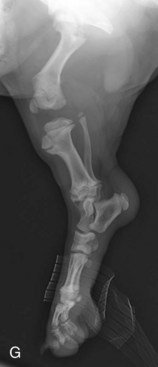

Left: X-rays from a 62 day old puppy (VeterinarianKey.com)

When you get your 8 week old puppies, please keep the below images in mind. Their bones do not even touch yet. They plod around so cutely with big floppy paws and wobbly movement because their joints are entirely made up of muscle, tendons and ligaments. Nothing is fitting tightly together or has a true socket yet.

Above: X-ray images showing open and closed growth plates in a puppy and adult dog.